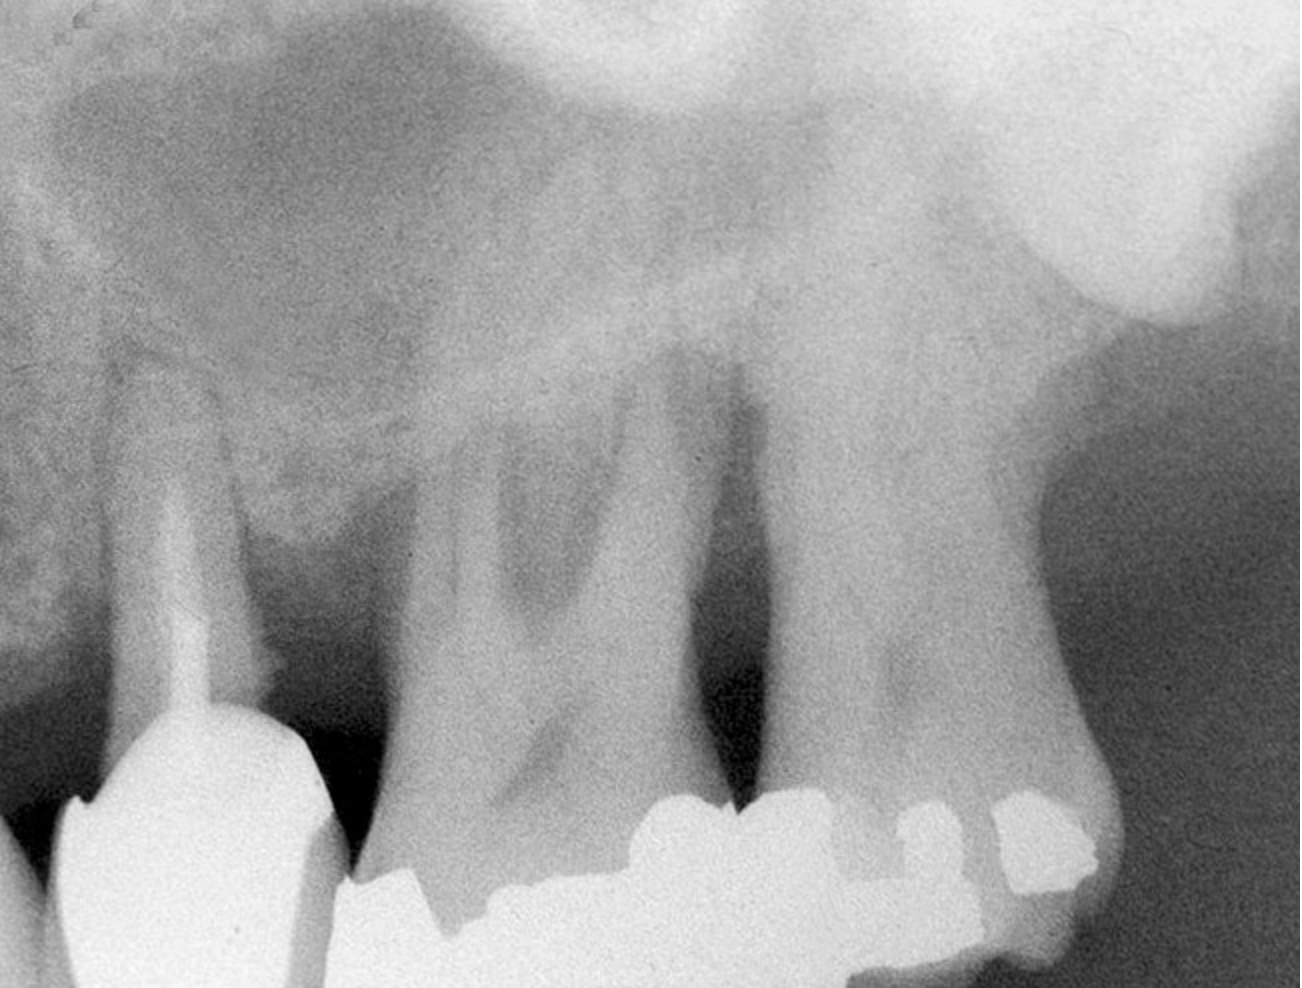

Sinus Floor Elevation in a Socket

The sinus floor elevation technique can be used when a tooth is extracted and there is not enough bone height to support an immediate implant (Figure 8, Figure 9 and Figure 10, Figure 11).32

Figure 8  At site No. 13 the second bicuspid had a hopeless prognosis; it was to be extracted and replaced with an implant after a transcrestal sinus floor elevation.

Figure 8

Figure 9: After the extraction, a 2.1-mm twist drill was used to drill within 1 mm of the subantral floor. A guide pin was placed and a radiograph was taken to ascertain if the drill stopped within 1 mm of the subantral floor.

Figure 9

Figure 10  The osteotomy was completed with the 2.1-, 2.8-, and 3.5-mm twist drills without penetrating into the sinus. After infracturing the subantral wall with a 3.5-mm osteotome, bone was added and the presence of a dome was confirmed with a radiograph.

Figure 10

Figure 11  Insertion of a 4.8-mm implant, which fit snugly and increased the surface area for future osseointegration.

Figure 11